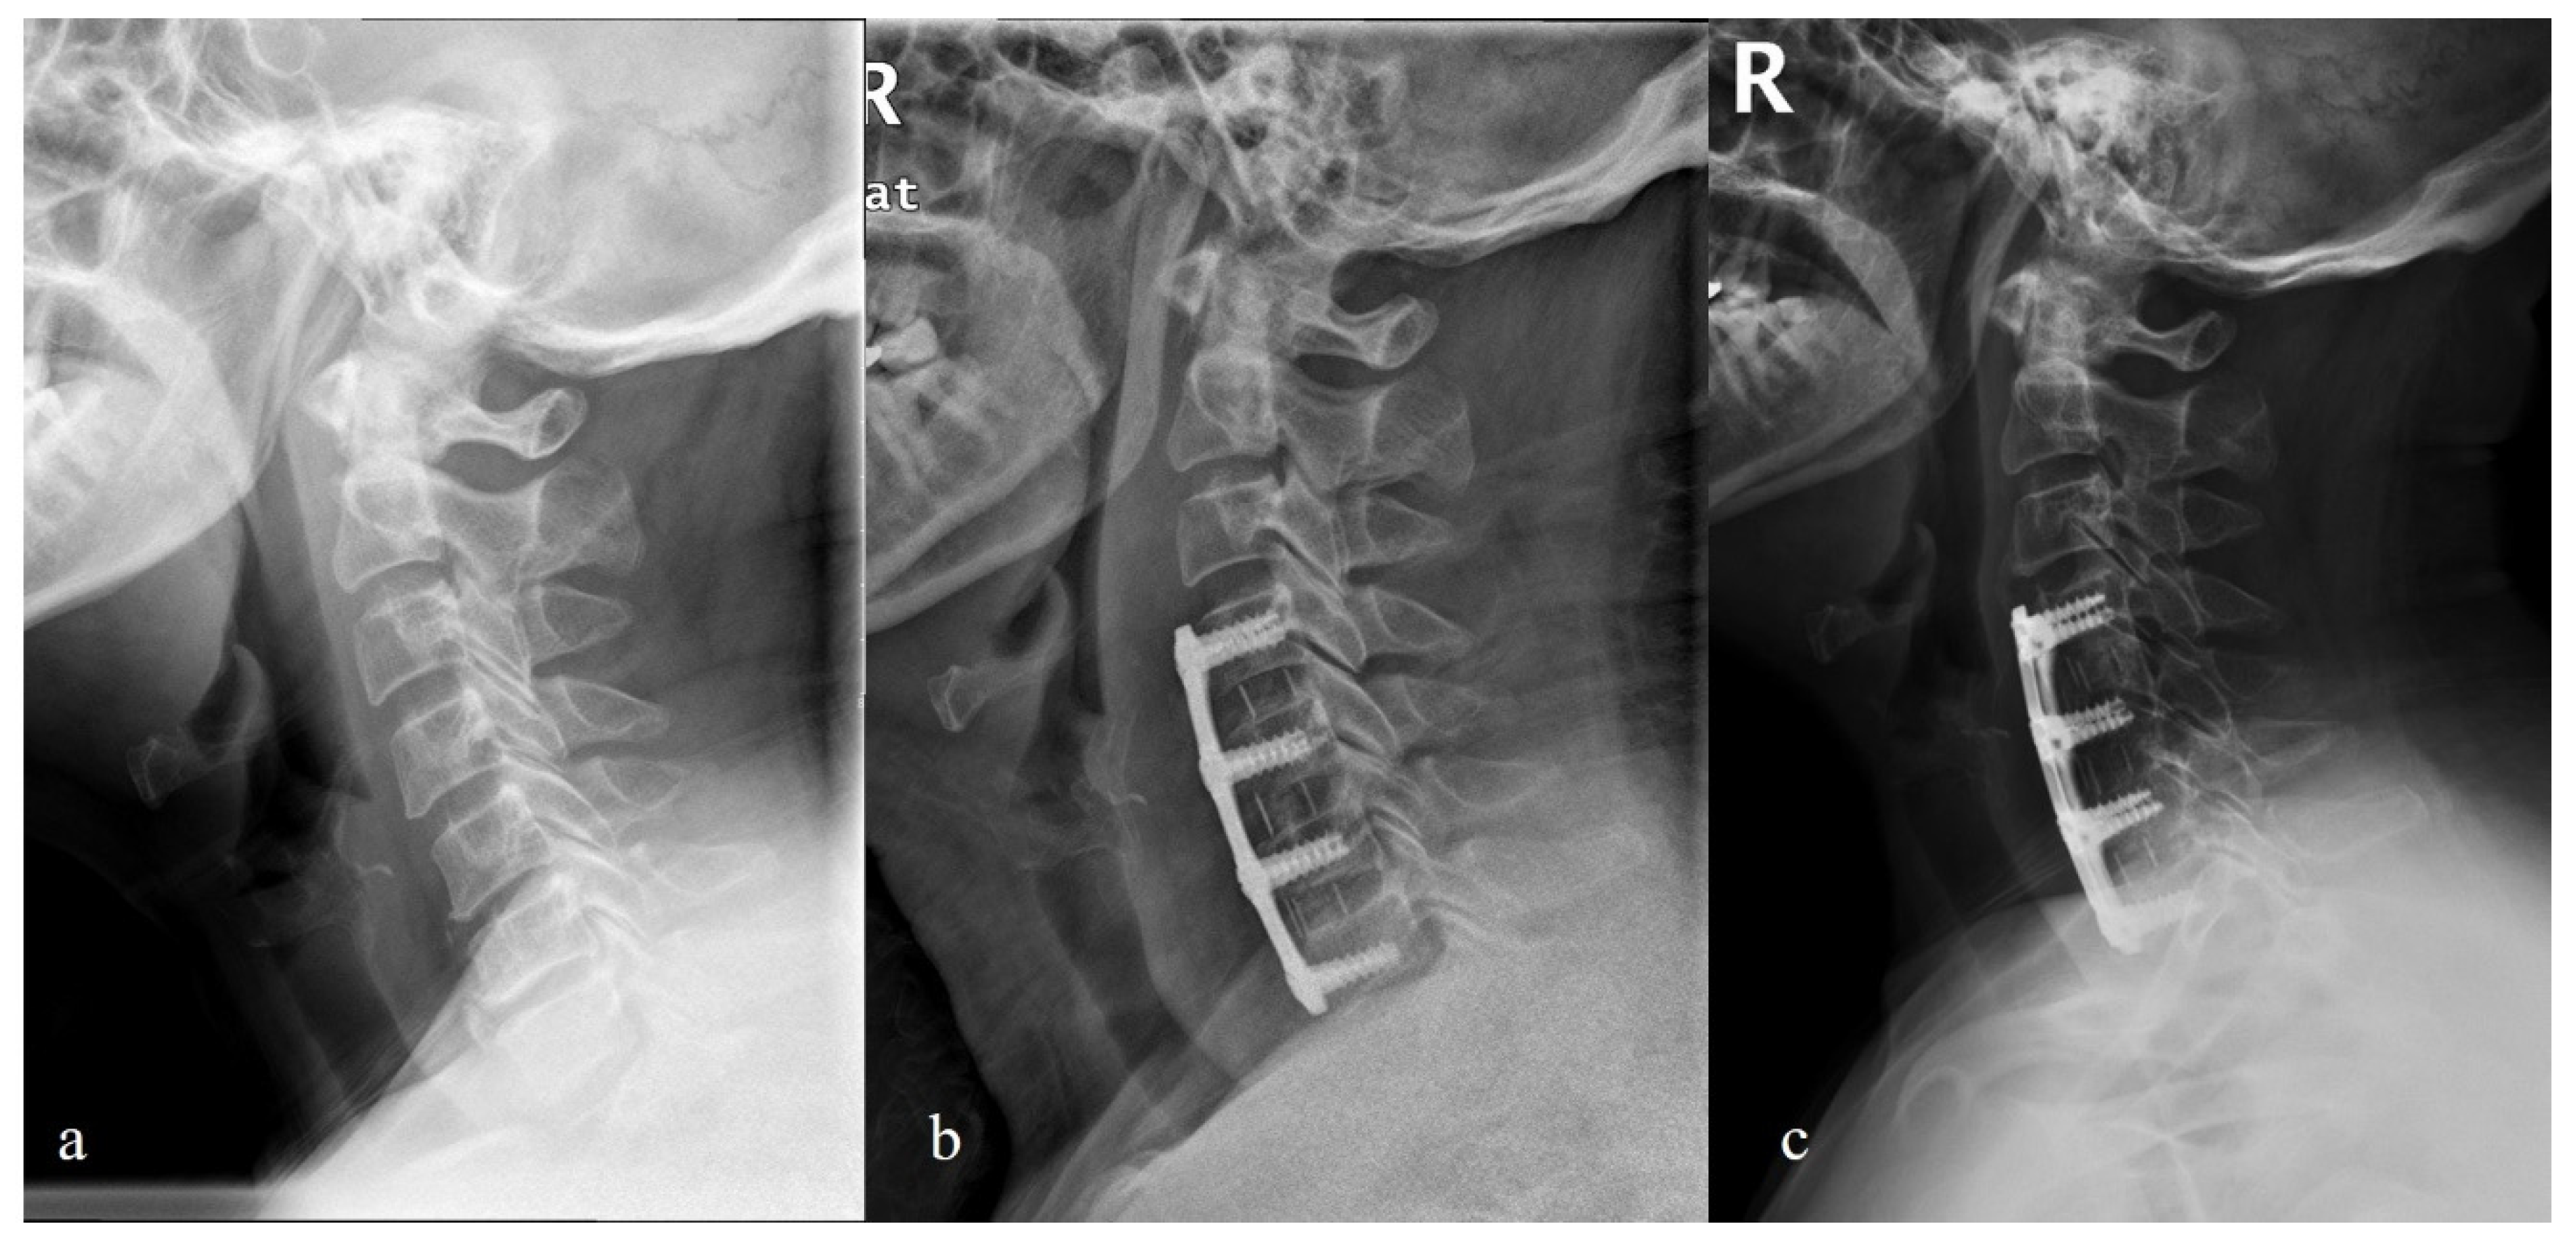

- Chen, Y.; Liu, Y.; Chen, H.; Cao, P.; Yuan, W. Comparison of Curvature Between the Zero-P Spacer and Traditional Cage and Plate After 3-Level Anterior Cervical Discectomy and Fusion: Mid-term Results. Clin. Spine Surg. 2017, 30, E1111–E1116. [Google Scholar] [CrossRef]

- Sun, B.; Shi, C.; Wu, H.; Xu, Z.; Lin, W.; Shen, X.; Wu, X.D.; Zhang, Y.; Yuan, W. Application of Zero-profile Spacer in the Treatment of Three-level Cervical Spondylotic Myelopathy: 5-year Follow-up Results. Spine 2020, 45, 504–511. [Google Scholar] [CrossRef]

- Xiao, B.; Wu, B.; Rong, T.; Cui, W.; Sang, D.; Liu, B. Clinical impact of 3-level anterior cervical decompression and fusion (ACDF) on the occipito-atlantoaxial complex: A retrospective study of patients who received a zero-profile anchored spacer versus cage-plate construct. Eur. Spine J. 2021, 30, 3656–3665. [Google Scholar] [CrossRef]